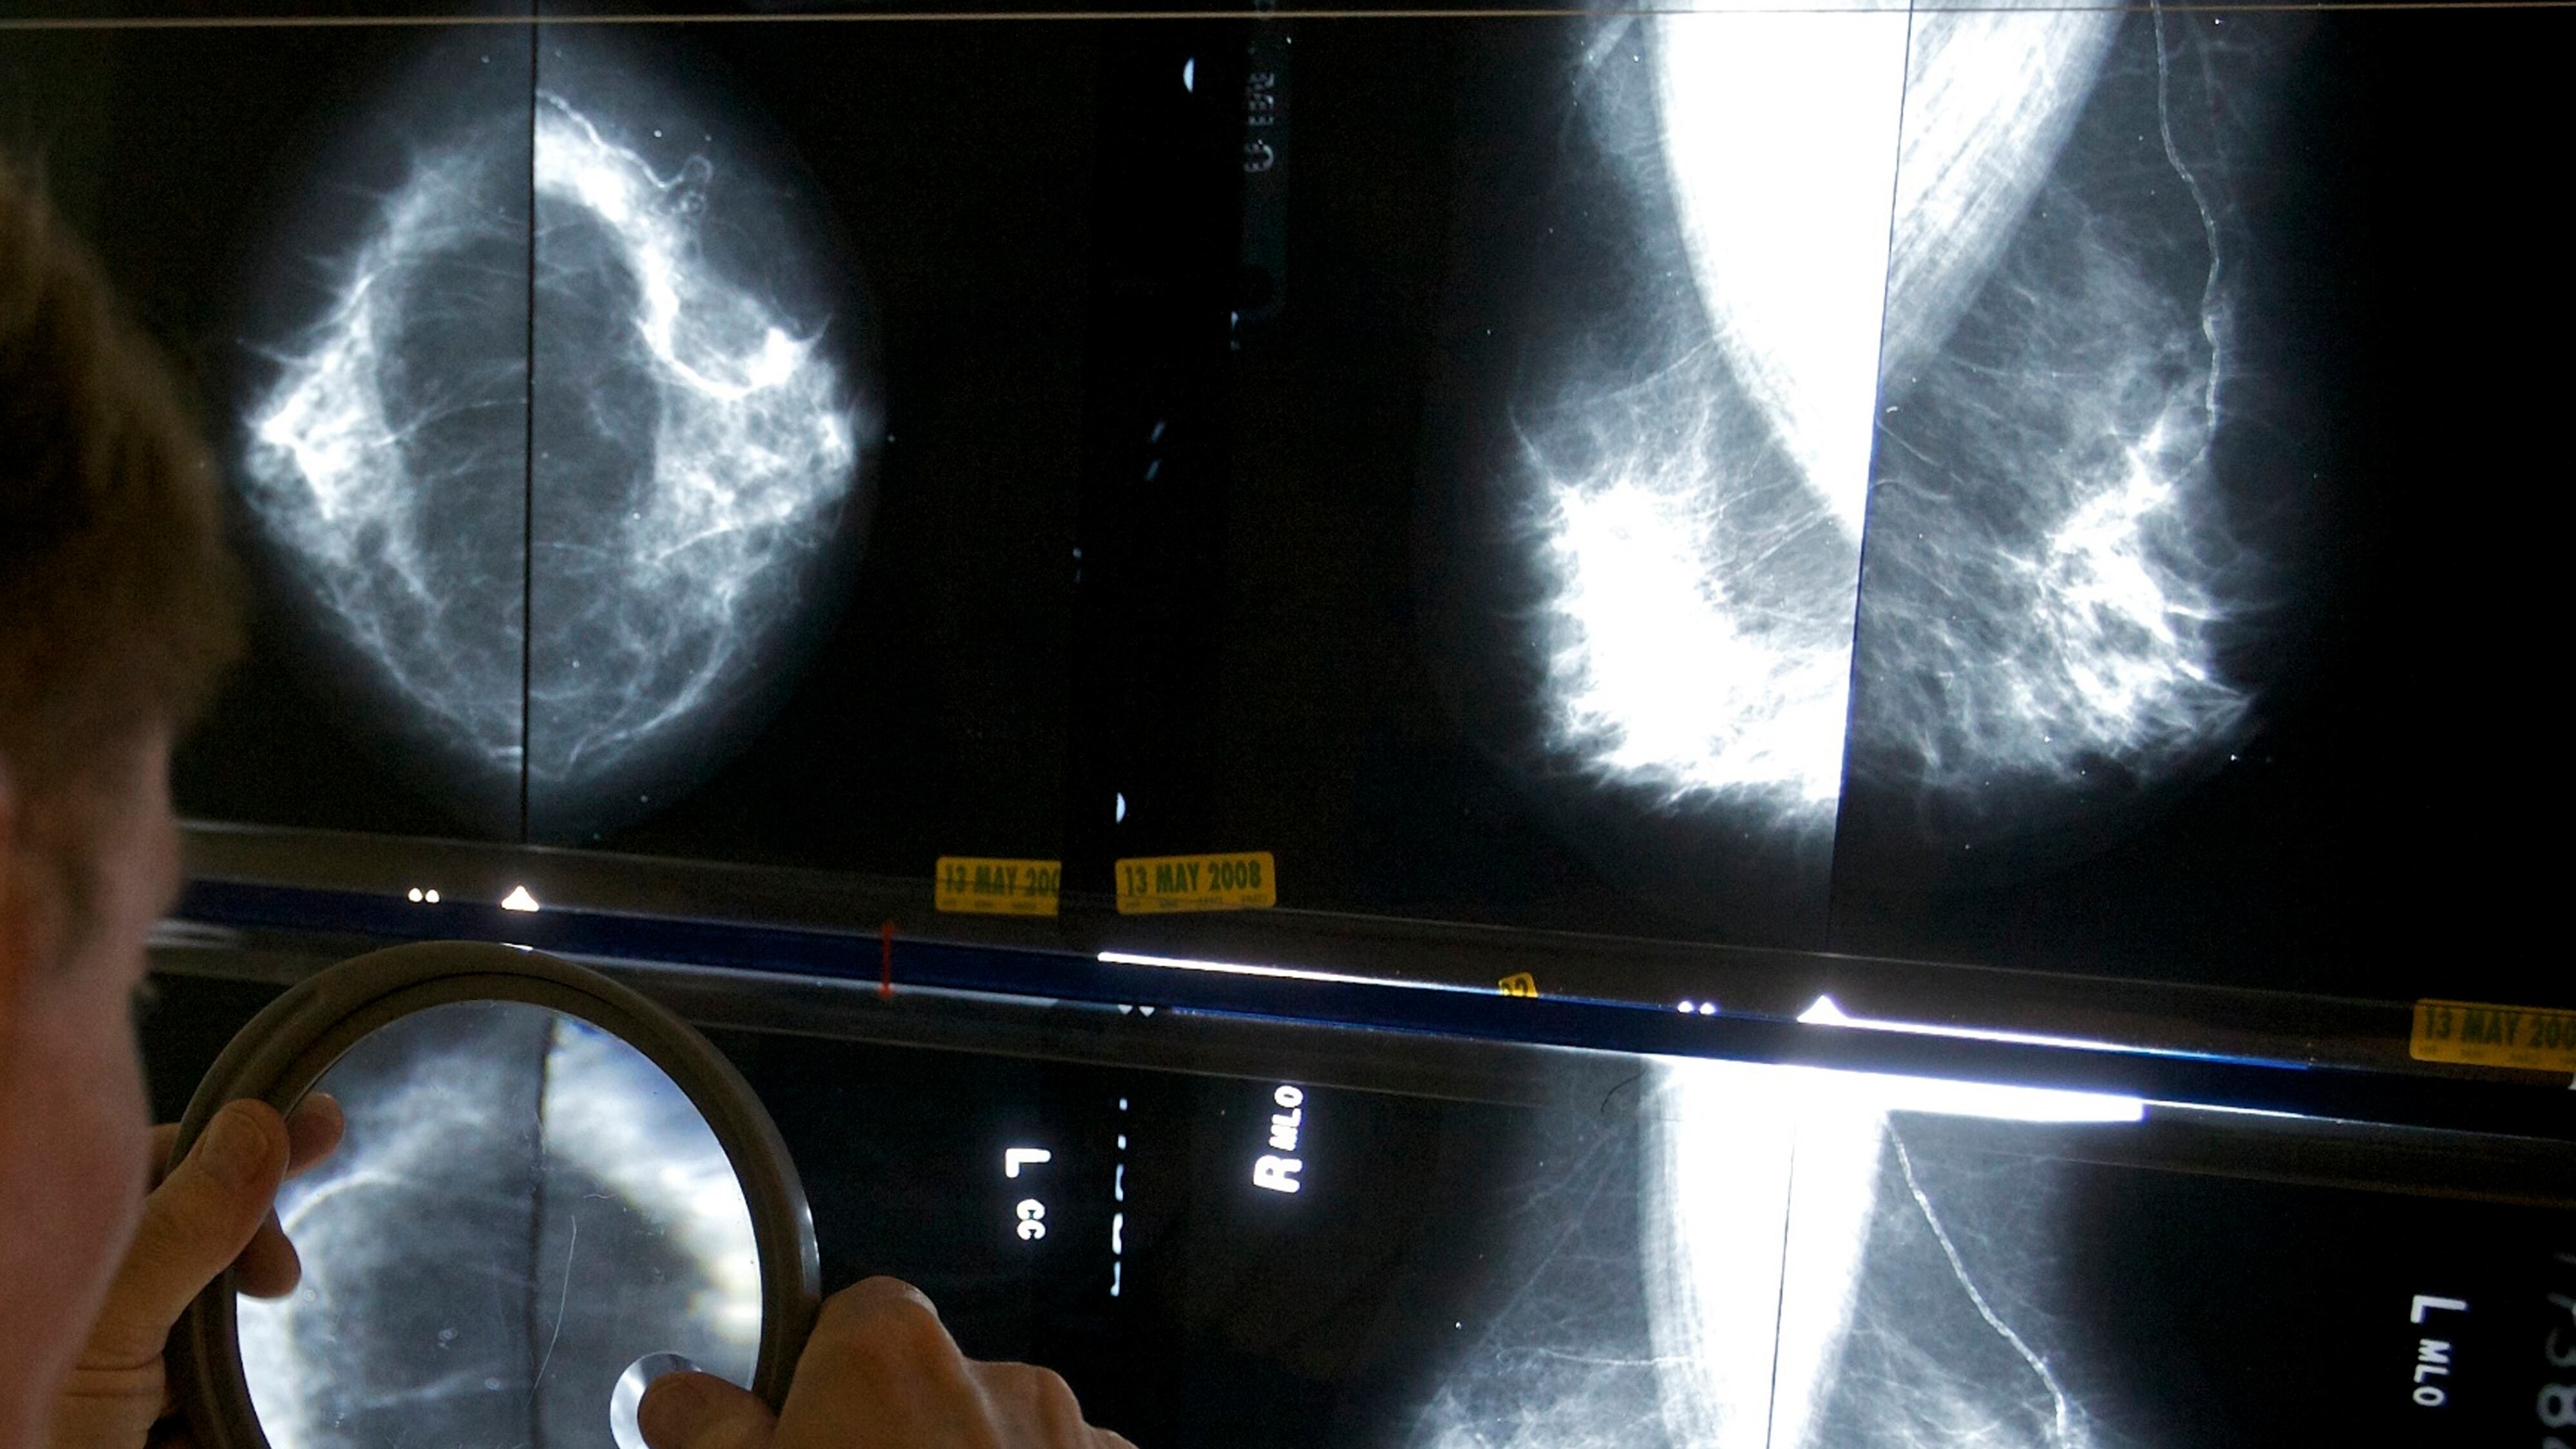

Las mujeres que se someten a cirugía por cáncer de mama a menudo también tienen lo que se llama una biopsia del ganglio linfático centinela, donde se eliminan algunos ganglios linfáticos en la axila para detectar la propagación del cáncer.

Pero la eliminación de ganglios linfáticos puede causar dolor persistente e hinchazón del brazo, por lo que se están realizando investigaciones para determinar cuándo se puede evitar. Un estudio en Europa el año pasado mostró que las mujeres mayores con tumores pequeños podrían evitar de manera segura la cirugía adicional.